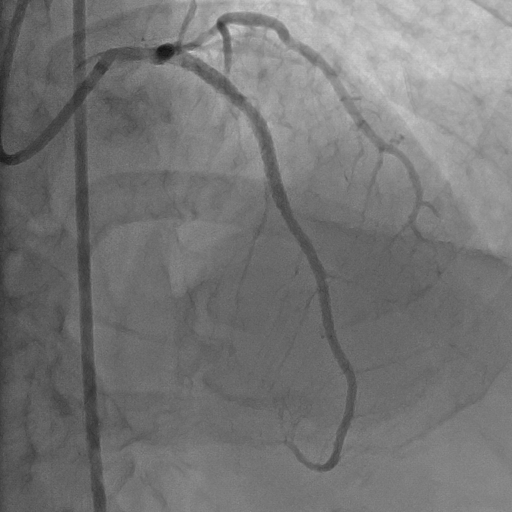

Hình ảnh: động mạch chủ trước khi phẩu thuật

Kết quả chụp mạch vành cho thấy mạch vành của bệnh nhân bị tắc hoàn toàn từ vị trí xuất phát của nhánh liên thất trước động mạch vành trái, trong khi đó nhánh động mạch mũ của động mạch vành trái và nhánh động mạch vành phải vẫn hoạt động bình thường.